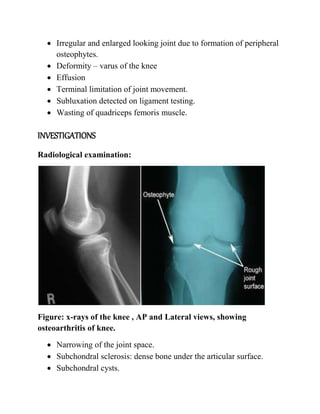

Radiological examination:

Figure: x-rays of the knee , AP and Lateral views, showing

osteoarthritis of knee.

 Narrowing of the joint space.

 Subchondral sclerosis: dense bone under the articular surface.

 Subchondral cysts.

 Osteophyte formation.

 Loose bodies.

 Deformity of the joints.